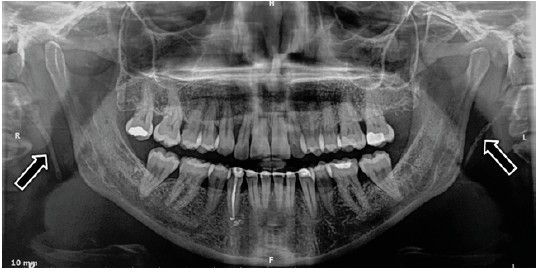

Los estudios disponibles coinciden en que las imágenes compatibles con calcificaciones carotídeas observadas en una ortopantomografía, ubicadas entre la 2ª-3ª-4ª vértebras, suelen ser posteriormente confirmadas como ateromas carotídeos mediante la técnica eco-Doppler7-12.

Estas calcificaciones que, generalmente se localizan en la bifurcación carotídea, se presentan como masas radiopacas en la región de la radiografía panorámica correspondiente a los tejidos blandos del cuello, en una zona aproximada entre las vértebras cervicales C2, C3 y C4, a una distancia aproximada entre 1 y 4 cm posteroinferior al ángulo mandibular13. Pueden variar en tamaño y forma, siendo lineales verticales, nodulares o heterogéneas, y pueden presentarse de manera unilateral o bilateral, así como ser únicas o múltiples13-15.

Por otro lado, algunos estudios indican que la presencia de calcificaciones carotídeas es más frecuente en pacientes con periodontitis13.